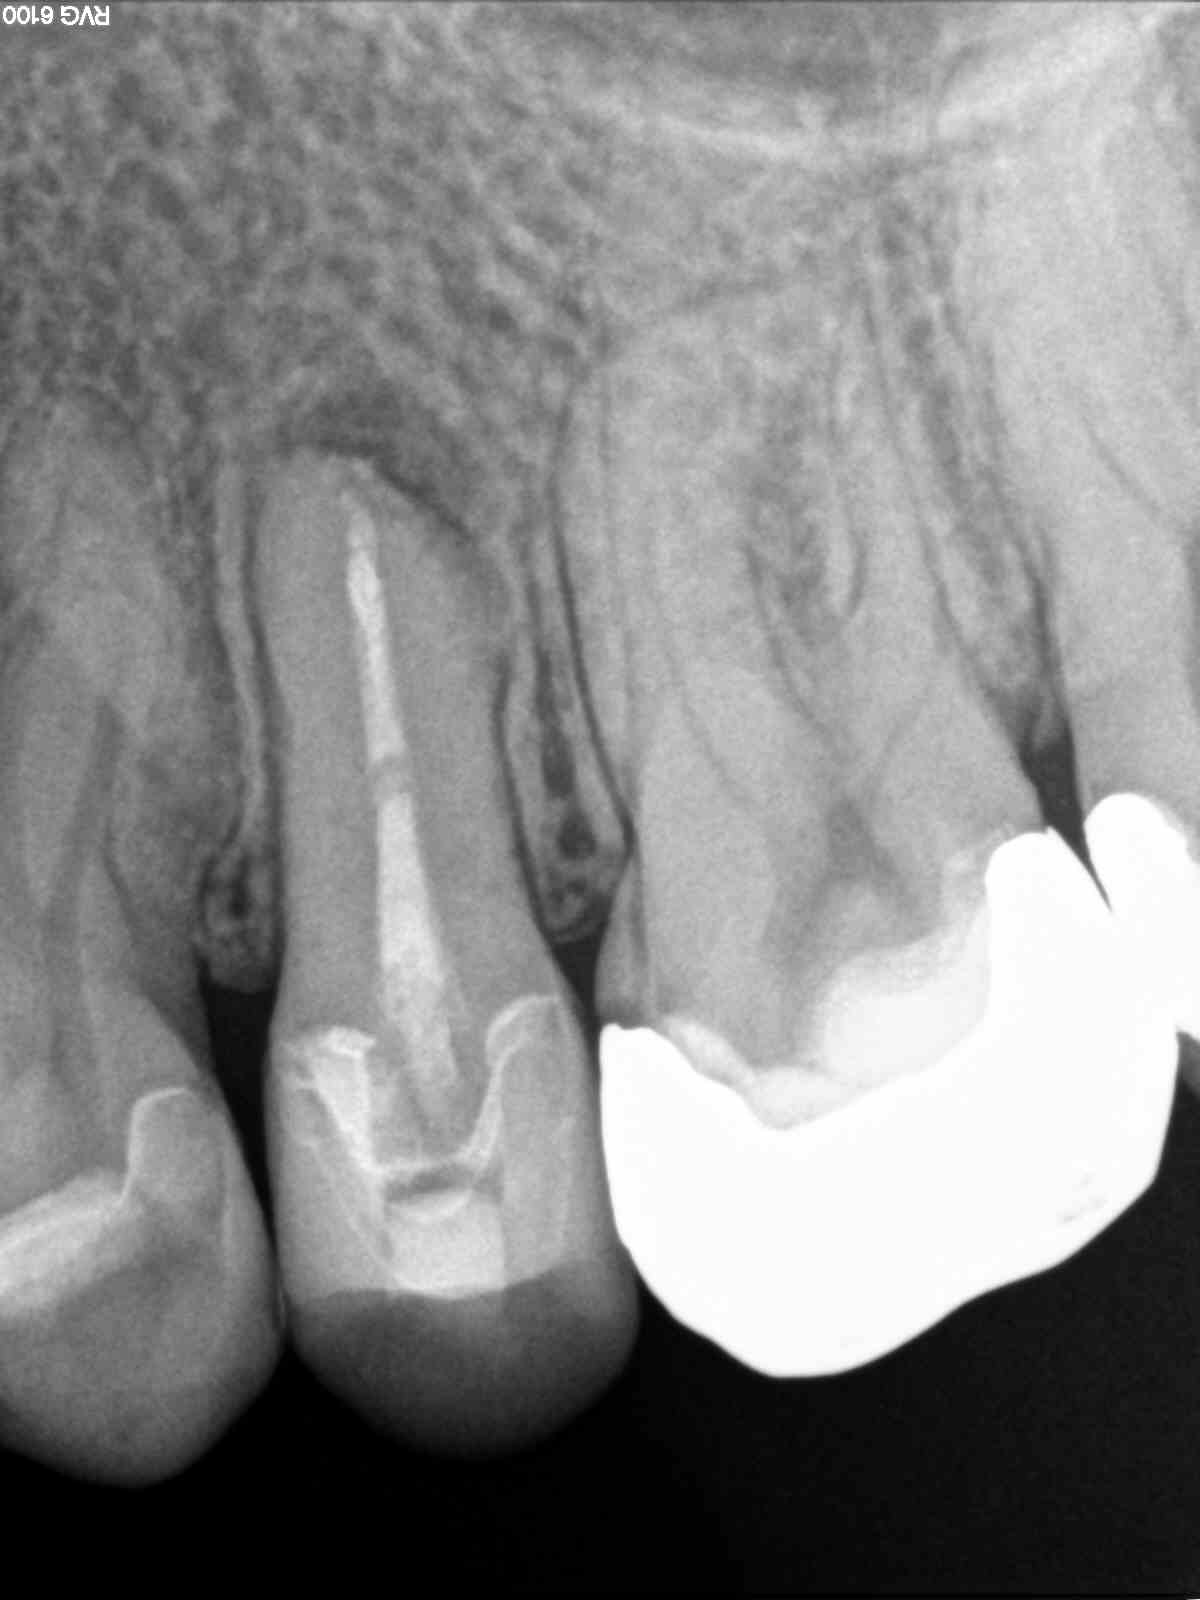

2-in-1 oder unerwarteter Abzweig